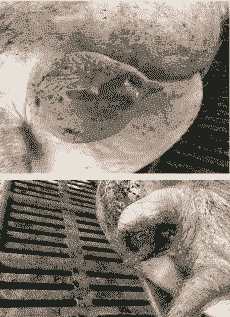

母猪外阴产后血肿是一种临床分娩并发症,可能由多种原因导致,包括胎儿过大、产道狭窄、助产损伤、老龄母猪子宫脆弱或仔猪胎位问题等。治疗方法包括: